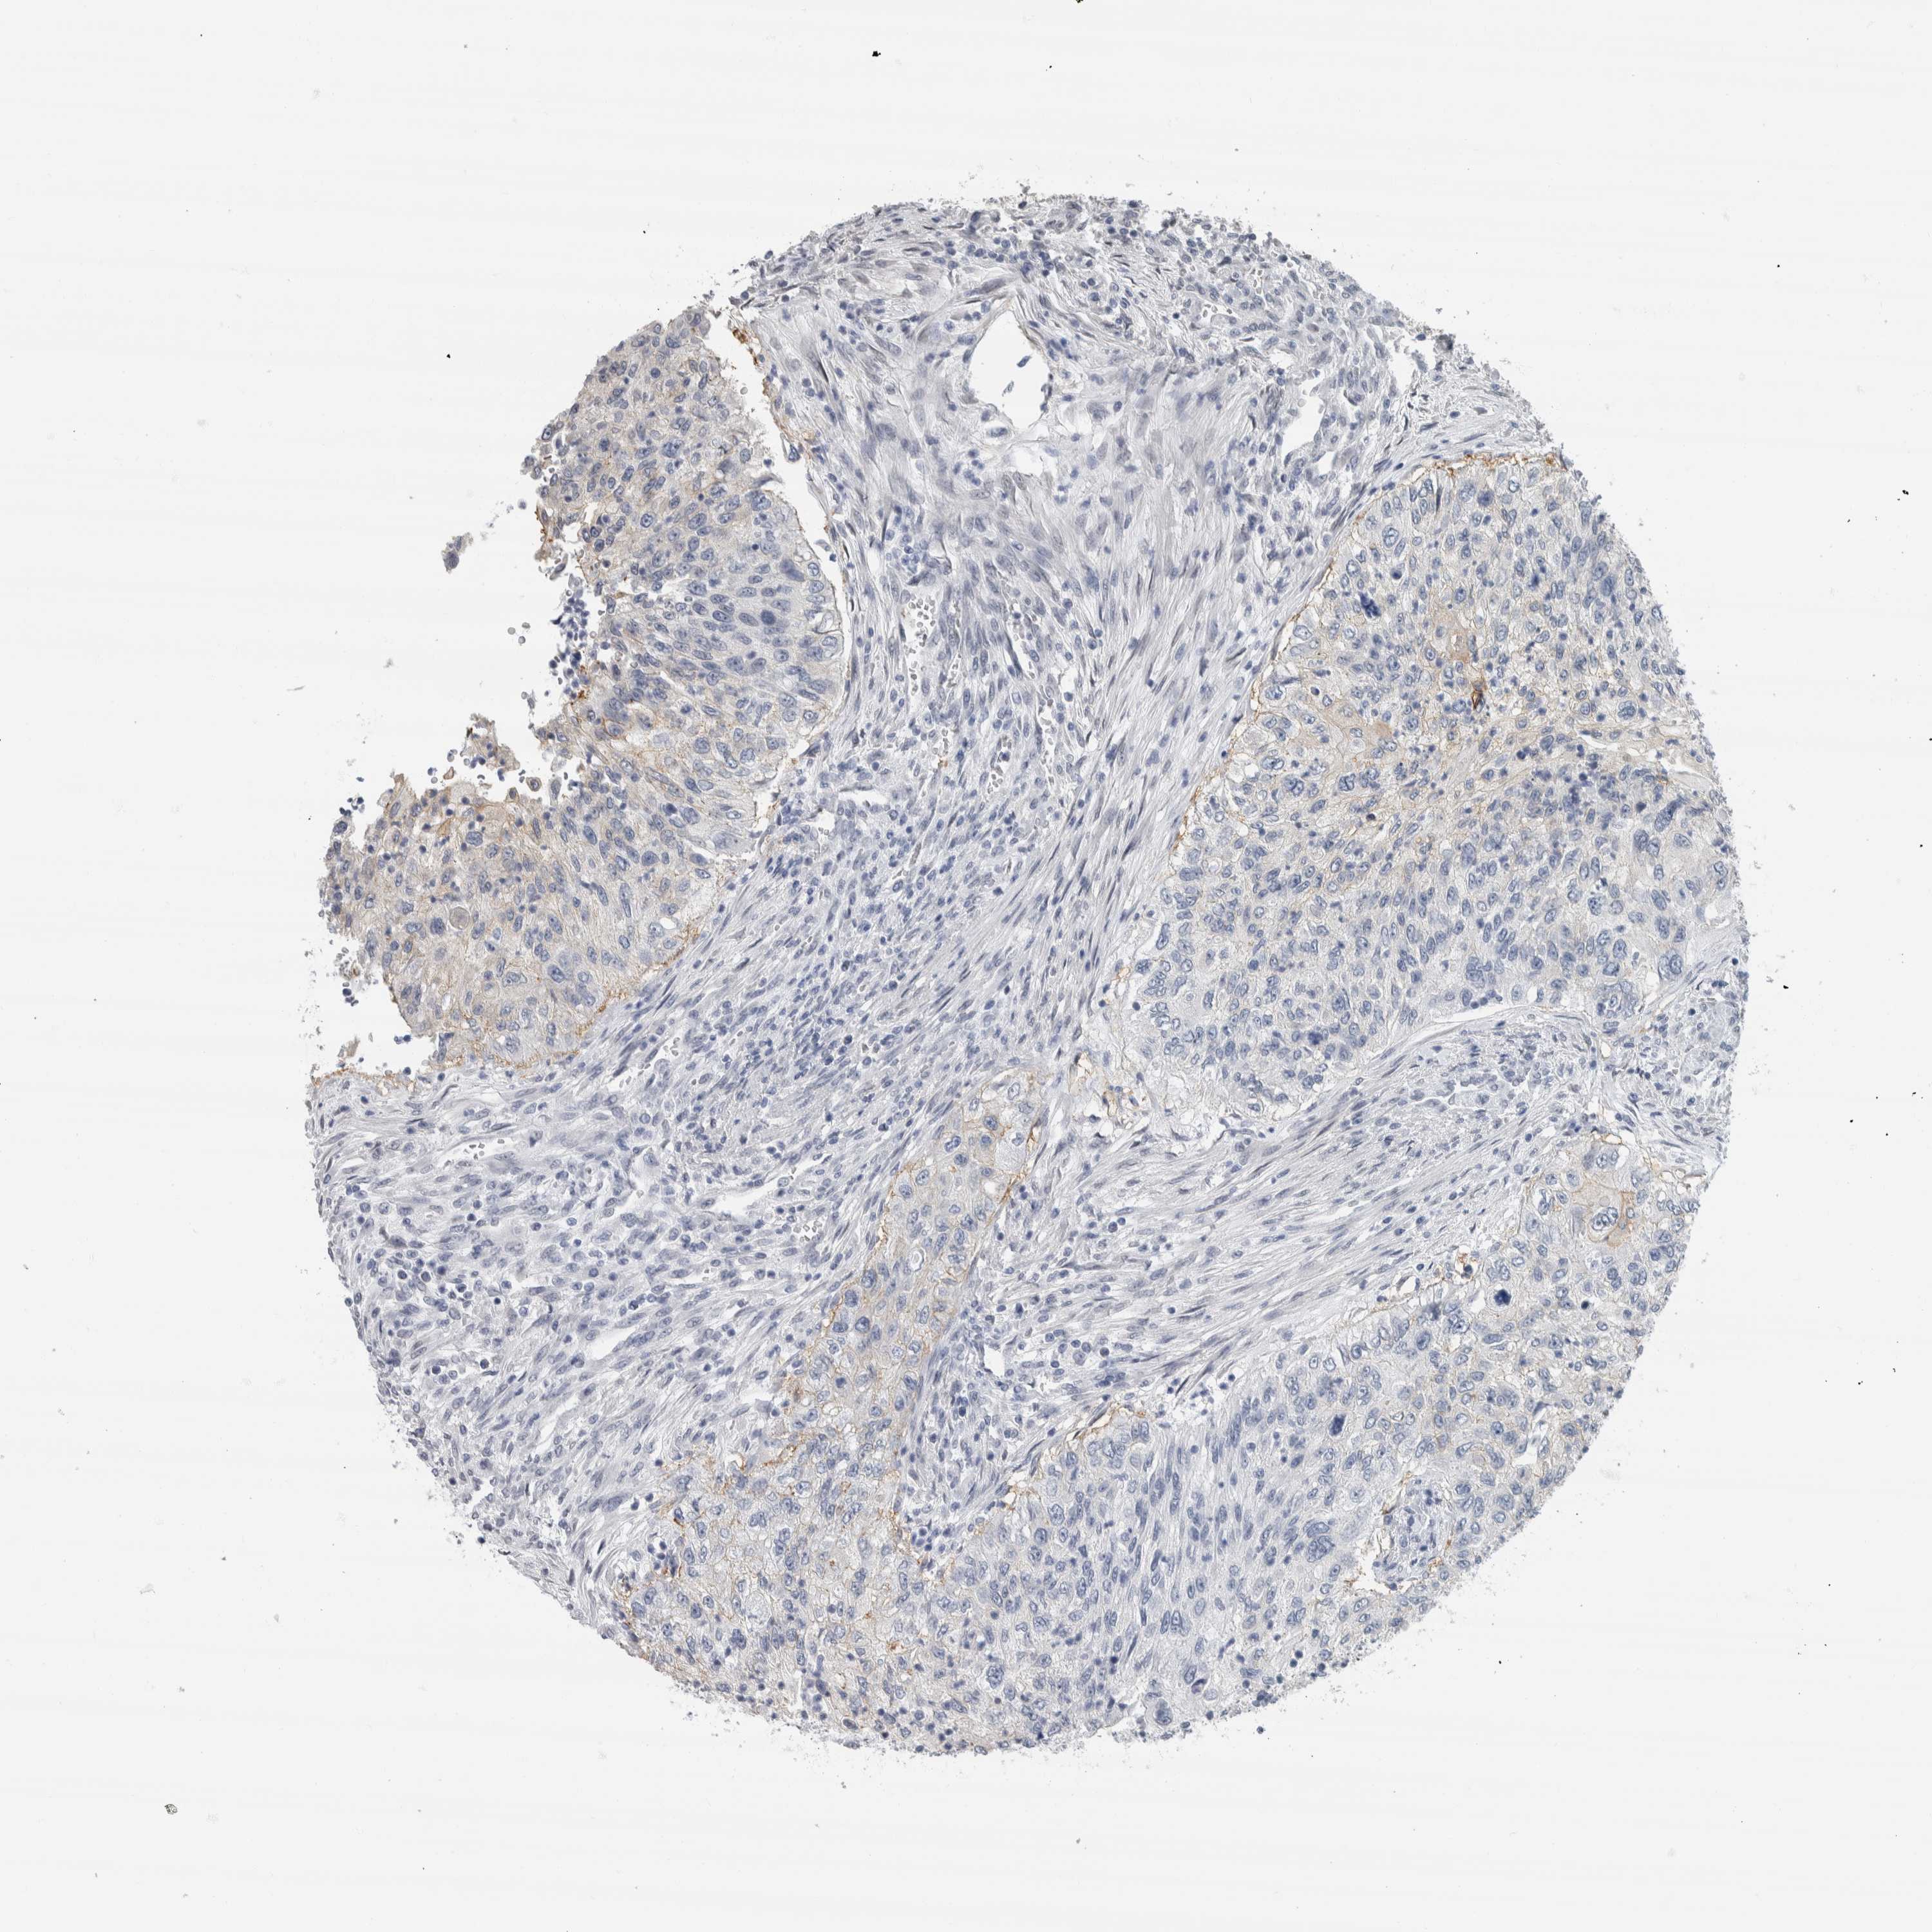

UROTHELIAL CANCER - Protein expressioni

A mouse-over function shows sample information and annotation data. Click on an image to view it in a full screen mode. Samples can be filtered based on level of antibody staining by selecting one or several of the following categories: high, medium, low and not detected. The assay and annotation is described here.

Note that samples used for immunohistochemistry by the Human Protein Atlas do not correspond to samples in the TCGA dataset.

Antibody stainingi

Antibody staining in the annotated cell types in the current human tissue is reported as not detected, low, medium, or high, based on conventional immunohistochemistry profiling in selected tissues. This score is based on the combination of the staining intensity and fraction of stained cells.

Each image is clickable and will lead to virtual microscopy that enables deeper exploration of all samples and also displays staining intensity scores, fraction scores and subcellular localization as well as patient and tissue information for each sample.

Antibody HPA022845

Antibody HPA023138

Antibody CAB010900

Antibody CAB012976

Staining

High

Medium

Low

Not detected

Intensity

Strong

Moderate

Weak

Negative

Quantity

>75%

75%-25%

<25%

None

Location

Nuclear

Cytoplasmic/membranous

Cytoplasmic/membranous,nuclear

Urothelial carcinoma, Low grade

Urothelial carcinoma, High grade